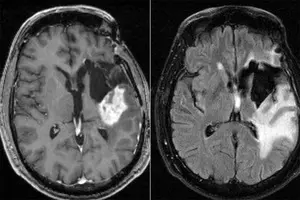

New Delhi, July 31 Potent immune cells have been found near glioblastomas, typically defined as highly aggressive and typically incurable brain tumours

Glioblastomas have a grim prognosis, with an average life expectancy of less than two years once all therapeutic options are exhausted. However, the new findings reveal that the body's immune system mounts a localised defence against these tumours. This discovery challenges the conventional understanding of the immune system as a holistic entity that sends immune cells throughout the body as needed.